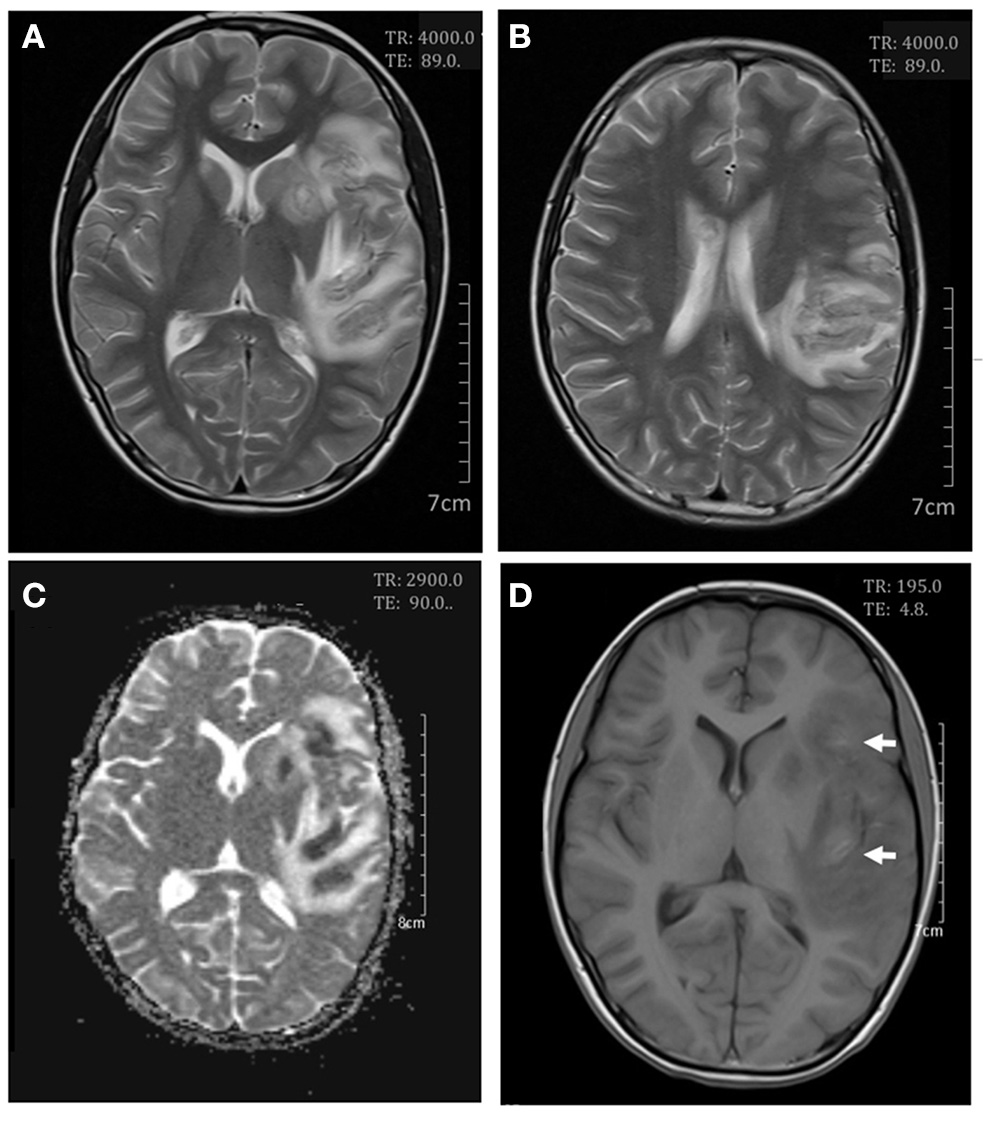

On day 7 after admission the patient appeared weak and ill, then the next day she exhibited dizziness, drowsiness, apathia, and dysarthria, and her temperature reached 37.9°C. The patient was given high-dose methylprednisolone pulse therapy (30 mg/kg/day) for 3 days. On day 9 the second cerebral MRI showed rapid progress (Figure 2), with multi-focal abnormal signals mainly involving white matter (bilateral temporal, cerebellum, insular lobes, and basal ganglias; left frontal and parietal lobes; right corpus callosum). The signals were hyperintense on fluid-attenuated inversion recovery (FLAIR). Cyclophosphamide (8.5 mg/kg/day for 2 days) and intravenous immunoglobulin (2 g/kg) were initiated in the therapy. On day 10 the patient showed significant improvements in all clinical conditions, including the rashes. On day 13 the third MRI demonstrated small infarcts in the left lentiform nucleus, left frontal lobe, temporal lobe, insular lobe, parietal lobe, and right corpus callosum, revealed by decrease in apparent diffusion coefficient in the gray matter, and an increased swelling in the surrounding white matter (Figure 3). She was given intrathecal dexamethasone once a week for three times. The second pulse of high-dose methylprednisolone was administered 1 week after the first pulse. Cyclophosphamide and immunoglobulin were administered with an interval of 2 weeks. On day 25 she had a fourth MRI scan and achieved neuroimaging improvements (Figure 4). The patient was discharged on day 30, with prednisone and addition of hydroxychloroquine.

Figure 3

Cerebral magnetic resonance imaging on day 13. Axial T2-weighted scan showed an increase in white matter swelling (A,B). Apparent diffusion coefficient maps demonstrated infarcts in the left lentiform nucleus and the frontal, temporal, insular, and parietal lobes (C). Axial T1-weighted scan showed small areas of hemorrhages in the frontal and insular lobes (D).